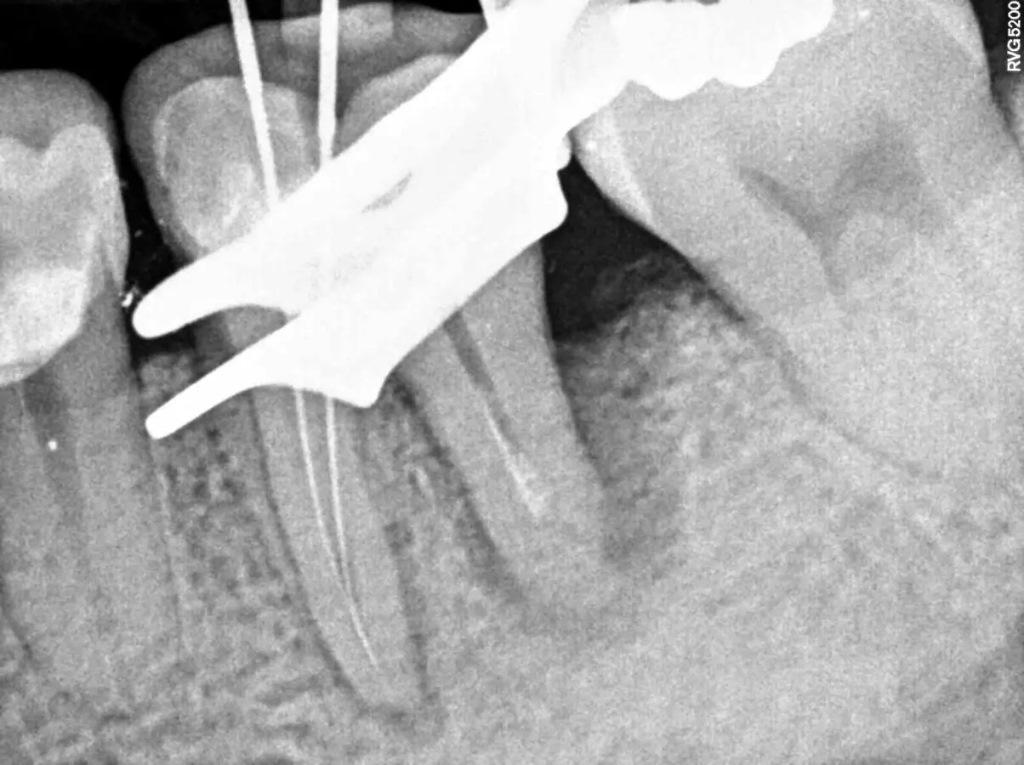

После этого с пациентом была обсуждена процедура гемисекции, и он дал свое полное согласие на ее проведение. Сначала дистальный канал был осторожно промыт гипохлоритом натрия в концентрации 5%, а затем обработан гидроксидом кальция (фото 3). При повторном посещении через 15 дней буккальный абсцесс отступил (фото 4). Затем мезиальный корневой канал обрабатывали обычным способом, определяя рабочую длину с помощью электронного апексолокатора (Root ZX II, Morita), проводили инструментарий с помощью никель–титановых файлов (Pro-Flexi Files, Denco) и обтурировали гуттаперчевым материалом и биокерамическим герметиком с использованием техники одноконусной обтурации (CeraSeal, Мета Biomed). На полимерную сердцевину был нанесен композит с двойной полимеризацией CompCore AF, Premier Dental (фото 5-6).